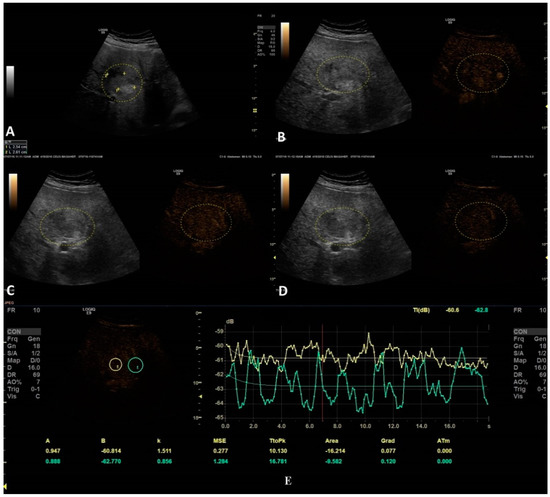

The last step consisted of applying the parametric imaging feature from GE-LOGIQ E9 [11] that enabled, according to a color-coded map, an evaluation of the perfusion kinetics of the lesion. This allowed us to better observe the enhancing pattern and the hyper- and hypo-enhanced areas of an FLL with the help of a colored display. Parametric imaging was used in the third step, with the intention to correctly differentiate the type of lesion after the malignancy was established in step two. The arterial phase (10–20 to 30–45 s) of each inconclusive lesion was subject to PI and classified according to the typical enhancement pattern explained in Table 1 [1] (Figure 4 and Figure 5).

Different colors were used to define different arrival times, as shown in Figure 6. As a result, a color-coded map was superimposed over the B-mode image.

Figure 6. Arterial phase of CEUS is depicted in frame (A). In frame (B), parametric imaging was applied, thus better documenting the arrival time of bubbles by using color coding, as shown in the color-coded bar.